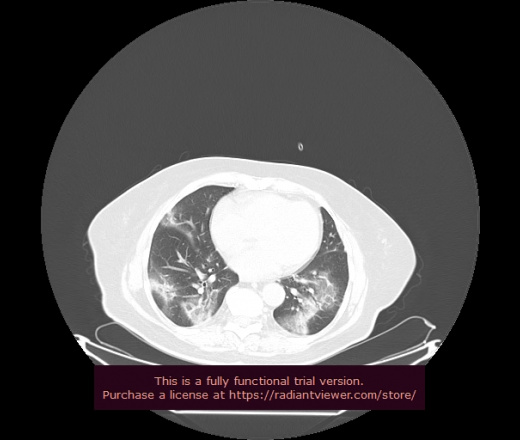

Уважаемые коллеги, если имеется интерес, сможете ли Вы спрогнозировать дальнейшее +-одинаковое течение процесса у 4 данных разных пациентов? Зацепиться где-то можно очень просто, где-то нельзя.